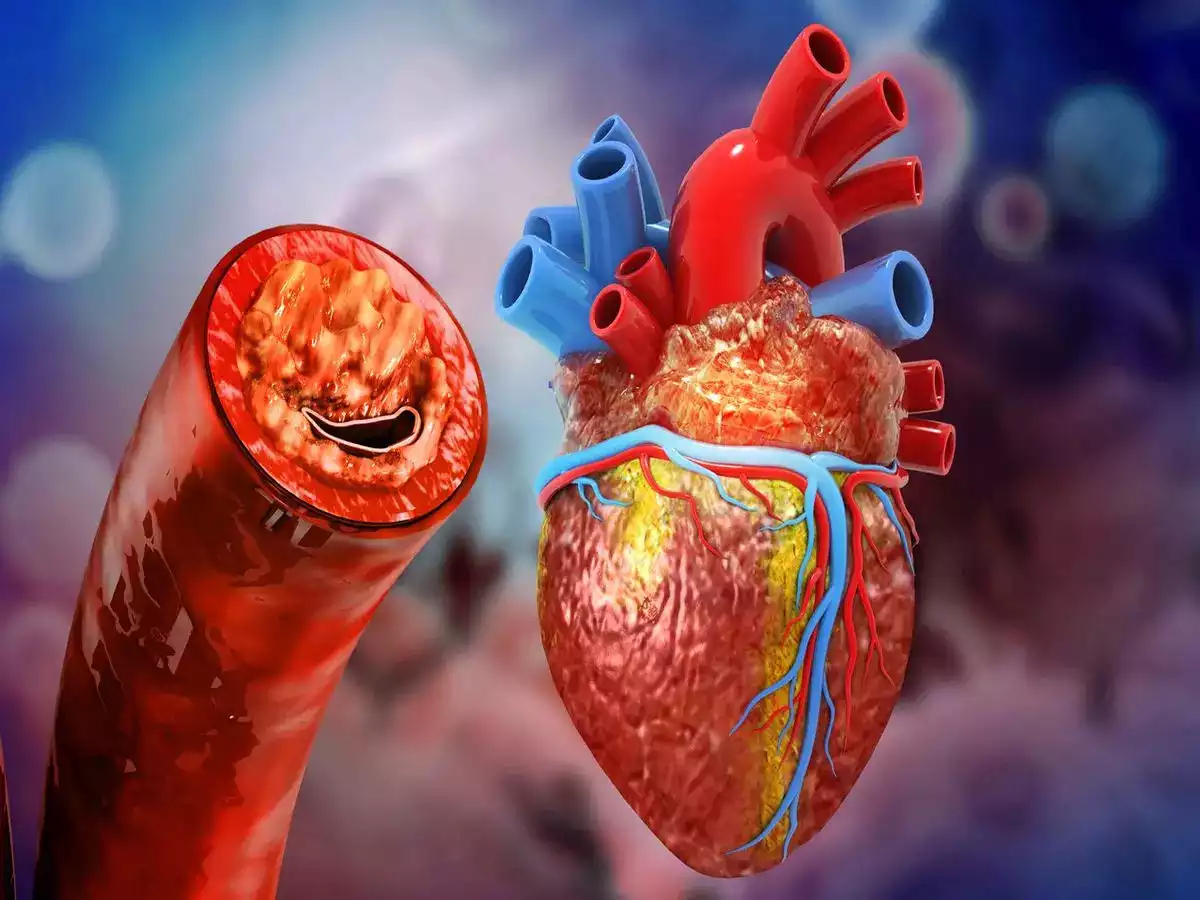

हार्ट ब्लॉकेज

रोजाना सुबह के समय कपालभाति करना काफी लाभकारी माना जाता है, इससे शरीर की कई बीमारियां चुटकियों में दूर हो जाती है. इसको रोजाना करने से हार्ट ब्लॉकेज जैसी बीमारियां दूर हो जाती है.